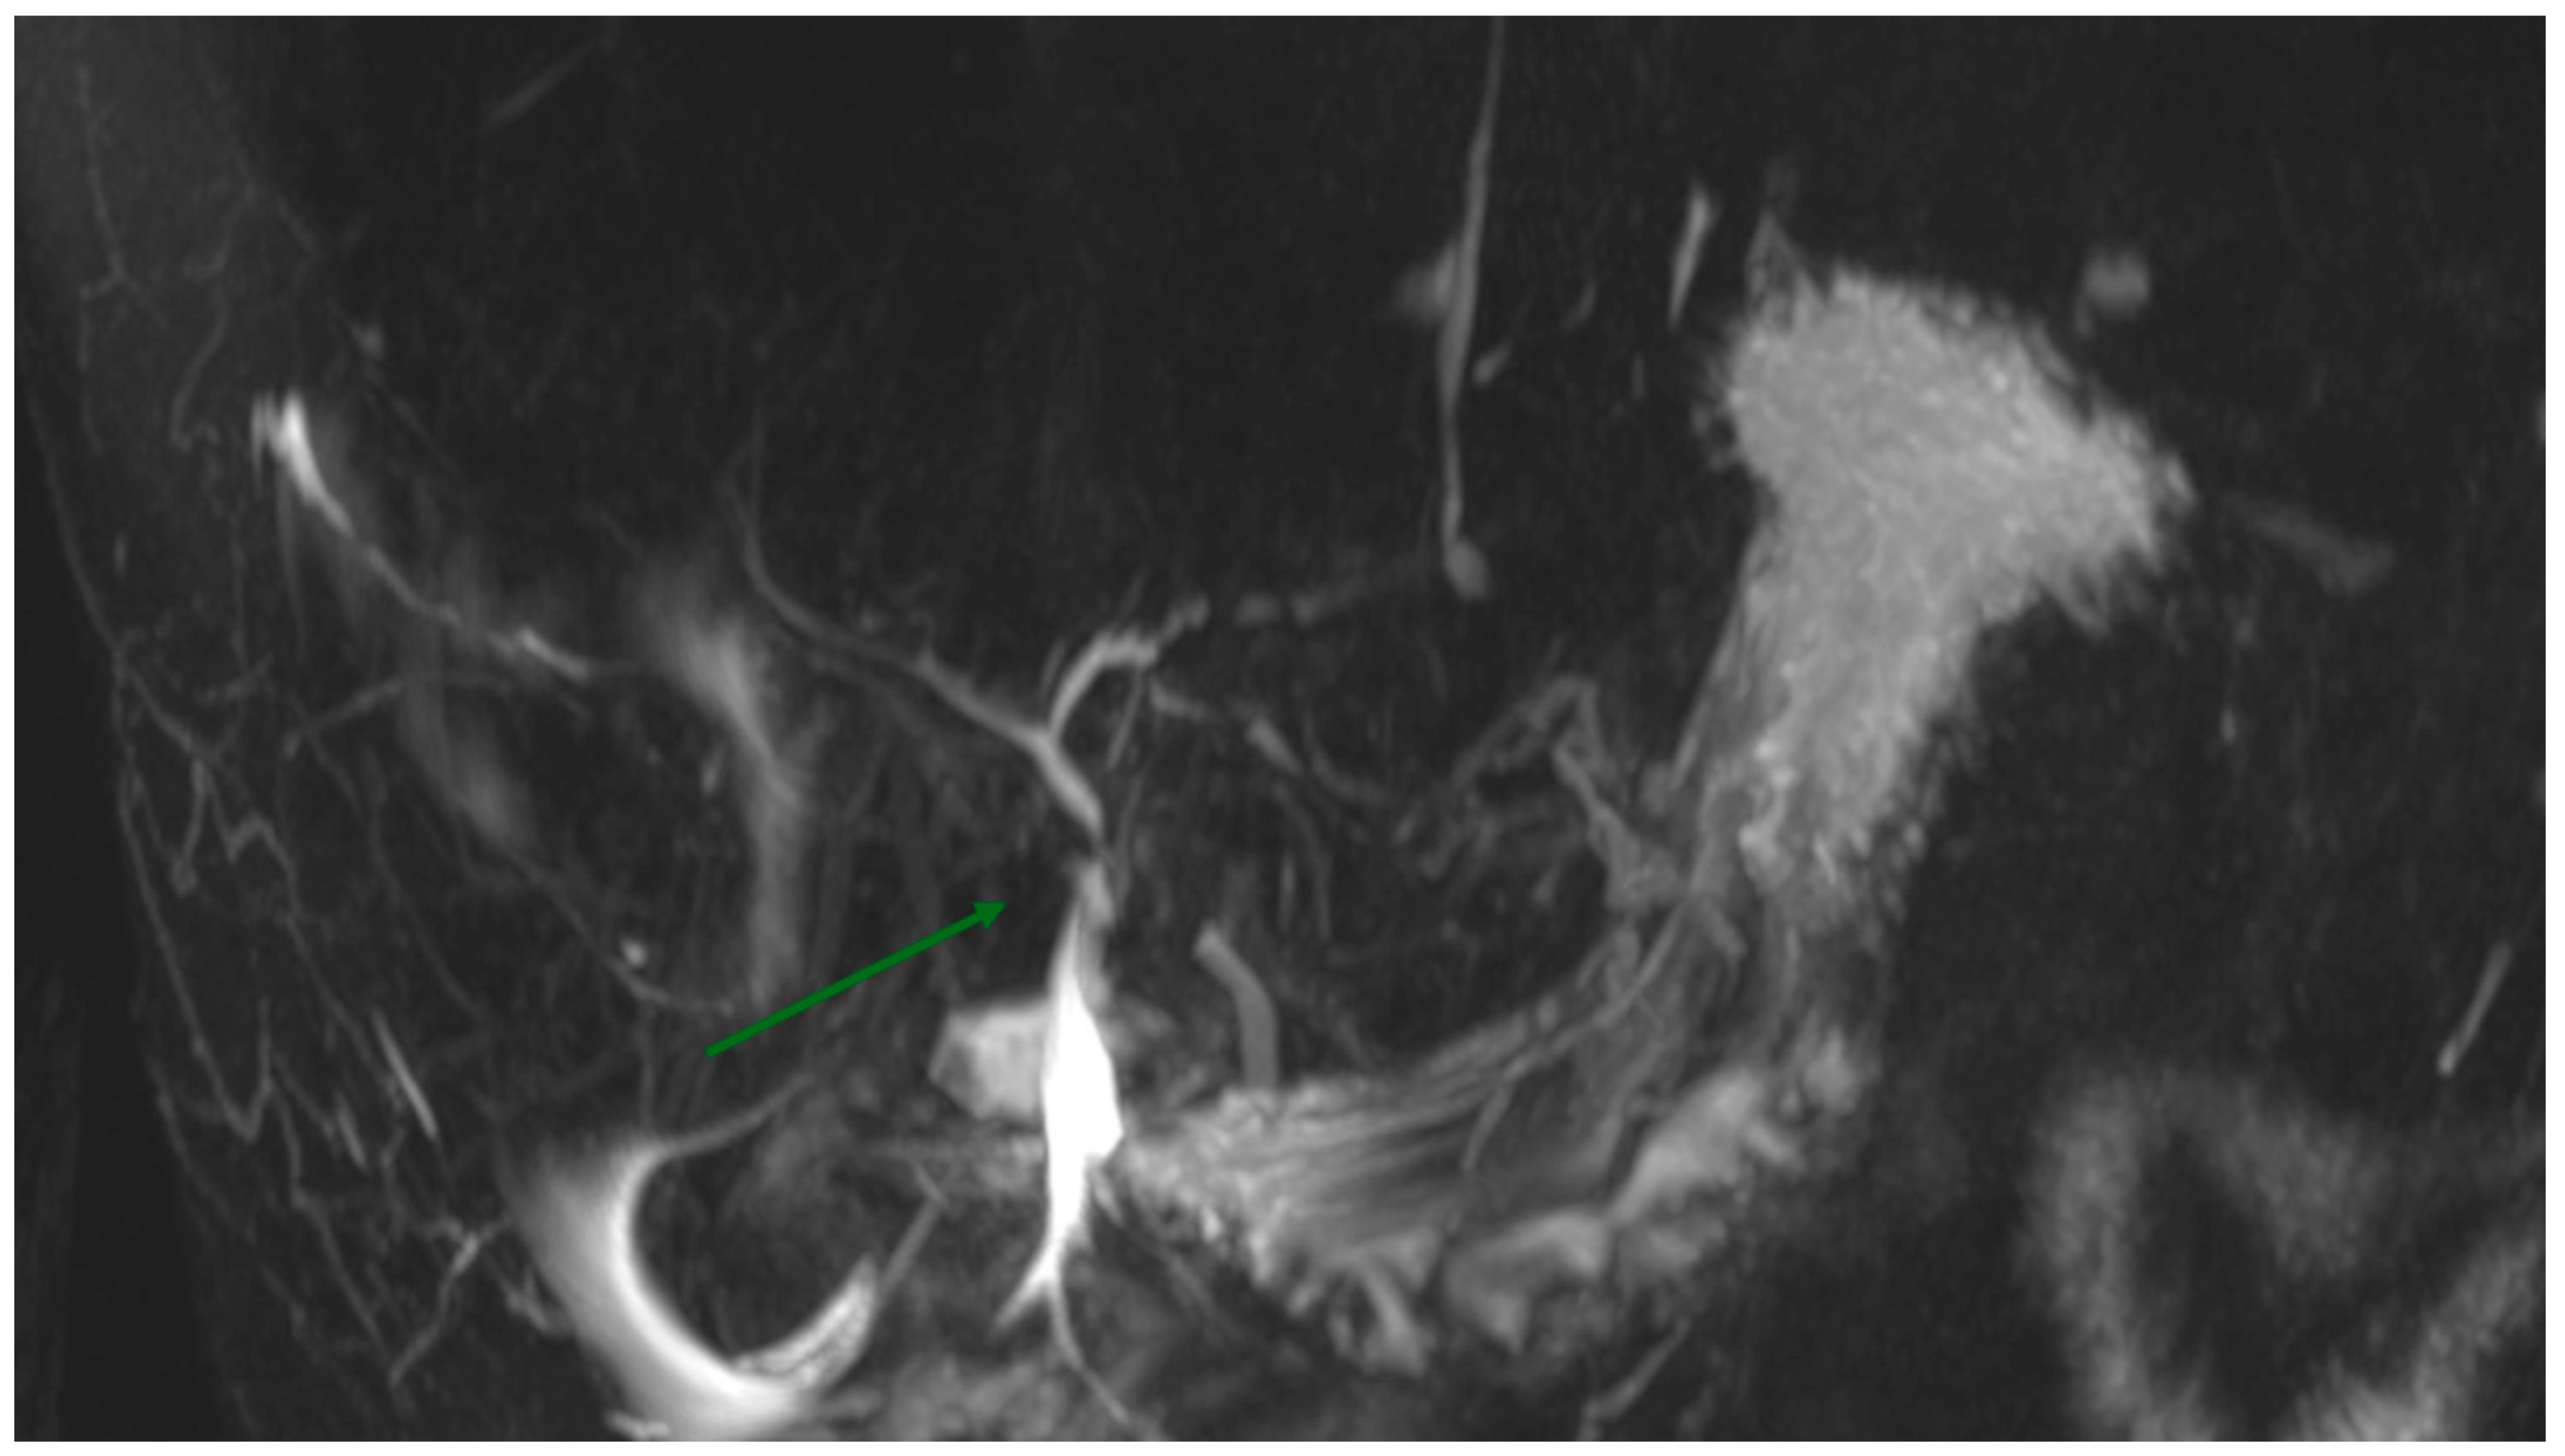

2. Case Presentation